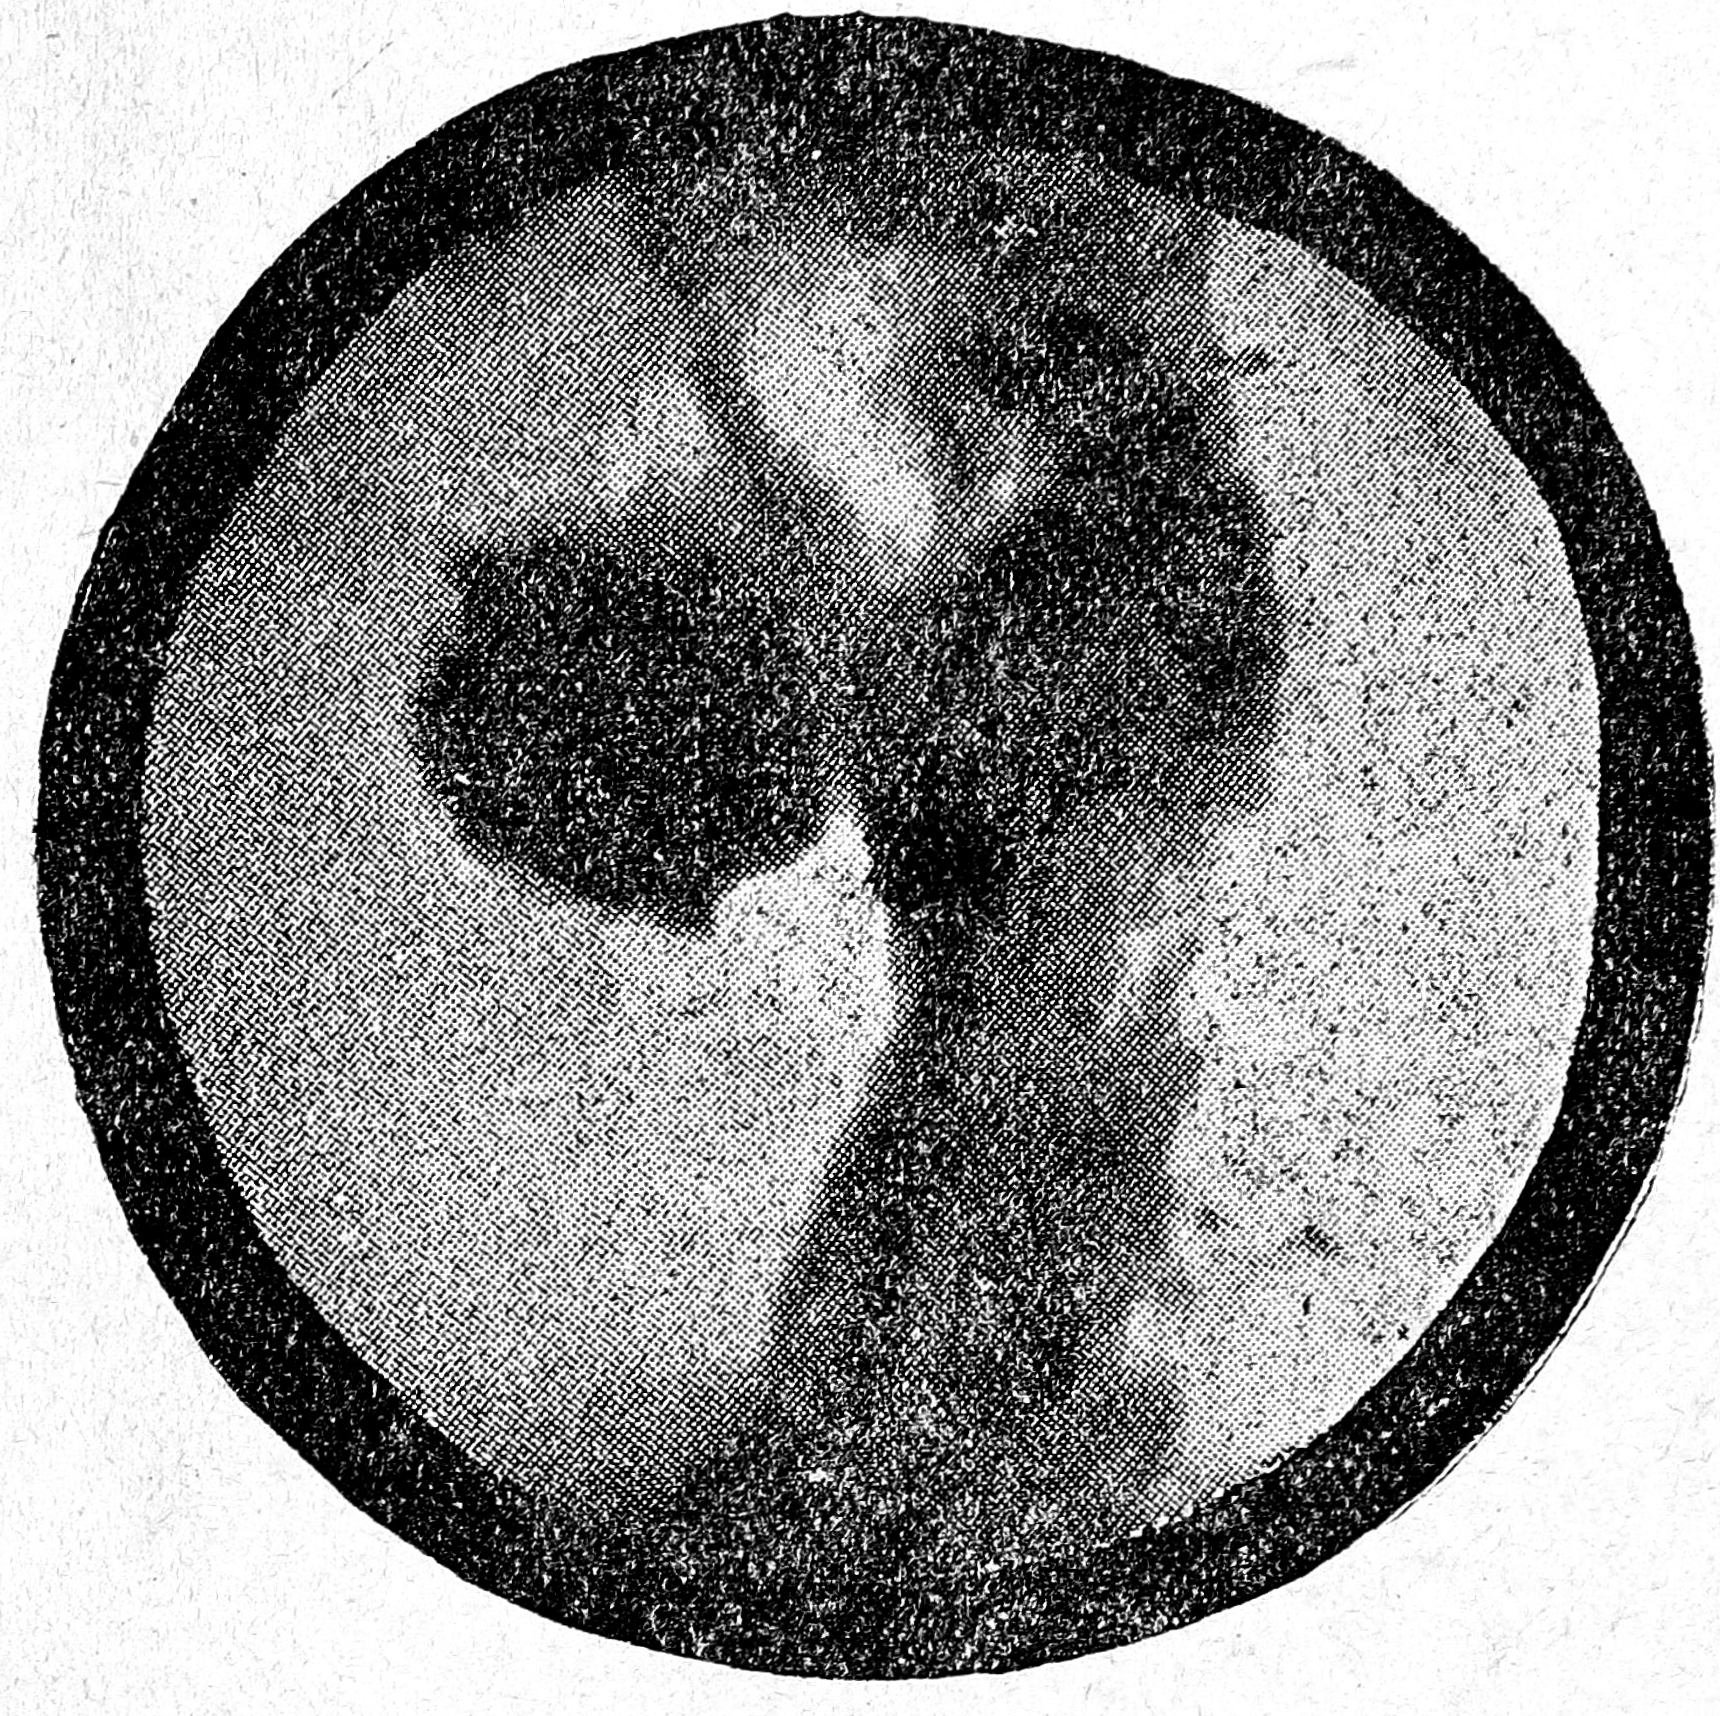

Б-ной С., 43 лет, рабочий-медик, истор. бол. № 12208, поступил в клинику 1|ХII 33. Болен 9 лет периодически появляющимися болями в подложечной области через 20—30 минут после еды, изжогой, рвотой. Явления эти продолжаются обычно 2—3 месяца и исчезают, чтобы через 6—7 месяцев появиться вновь. Аппетит всегда хороший, за последние две недели сильные боли в подложечной области, отдающие в грудную клетку после еды, частая рвота. При исследовании значительная болезненность в подложечной области справа от средней линии при ощупывании и при поколачивании, мышечное напряжение здесь же. Фракционное исследование желудочного содержимого обнаруживает небольшую subaciditas, neutralrot выделился через 35 минут, секреция на повышение. В испражнениях скрытая кровь при повторном исследовании—отсутствует. Рентгеновское исследование 6/ХII,—желудок вытянутый—крючек с хорошо выраженными складками, также проецирующимися вытянутыми; в верхней трети малой кривизны проэцируется большой Ulcuskrater, резко болезненный. Рентгеновский диагноз—Ulcus ventriculi profundum (penetrans) (см. рентгенограмму № 1).

Рис. 1

29/XII. 33. Самочувствие больного хорошее, субъективных жалоб нет, небольшая только болезненность в подложечной области при глубоком надавливании.

Рентгеновское исследование: резкое уменьшение калибра язвенного кратера, болезненности в области ниши нет, межуточный слой небольшой, перистальтика умеренная, складки слизистой еще раздражены. Рентгенологический диагноз: Uleus ventriculi curvaturae minoris в стадии заживления (см. рентгенограмму № 2).

Рис. 2

20/1 34 г. Самочувствие больного остается хорошим. Рентгеновское исследование— явлений ниши не обнаружено; желудок глубоко перистальтирует, отмечается замытость складок желудочным слоем и их раздраженность в области бывшей ниши, болезненности не отмечается (см. рентгенограмму № 3).

Рис. 3

Таким образом, ниша огромных размеров, которую мы еще так недавно должны были считать подлежащей безусловно хирургическому лечению с резекцией желудка, исчезла под влиянием одного консервативного лечения и остались только явления гастрита и раздраженный желудок, т. е. определенная стадия гастропатии.

Как видно из прилагаемых рентгенограмм—огромная пенетрирущая ниша зажила в этом случае совершенно бесследно. Этот случай является лучшим обоснованием того, что консервативное лечение должно сопровождаться динамическим рентгеновским контролем, который и решит в последнем счете вопрос, можно-ли ограничиться консервативным лечением или больной подлежит оперативному вмешательству.